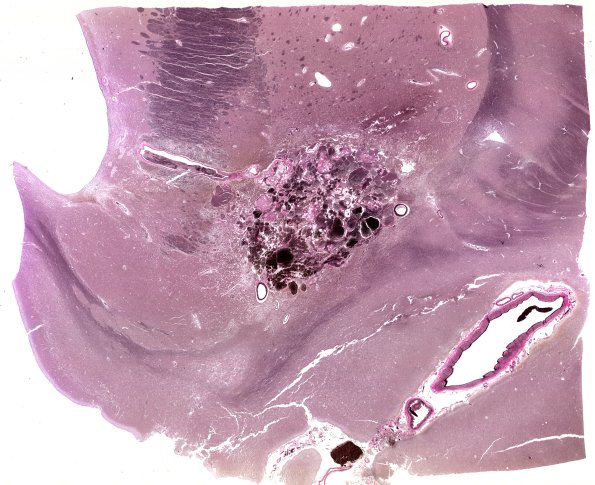

Cavernous Angioma

31E1 Cavernoma (Case 31) VVG WM

A whole mount of the cavernoma stained for elastic tissue. (elastin)